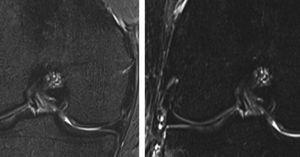

(left) STIR MR image (TI 205 ms) shows weak fat suppression of bone marrow. (right) STIR MR image (TI 220 ms) shows stronger fat suppression. By modulating TI, it is possible to adjust the strength of the fat suppression desired: a TI that is close to the exact nulling time will have the strongest fat suppression, whereas a lower or higher TI will have weaker fat suppression. Image dataset acquired at 3.0 Tesla.